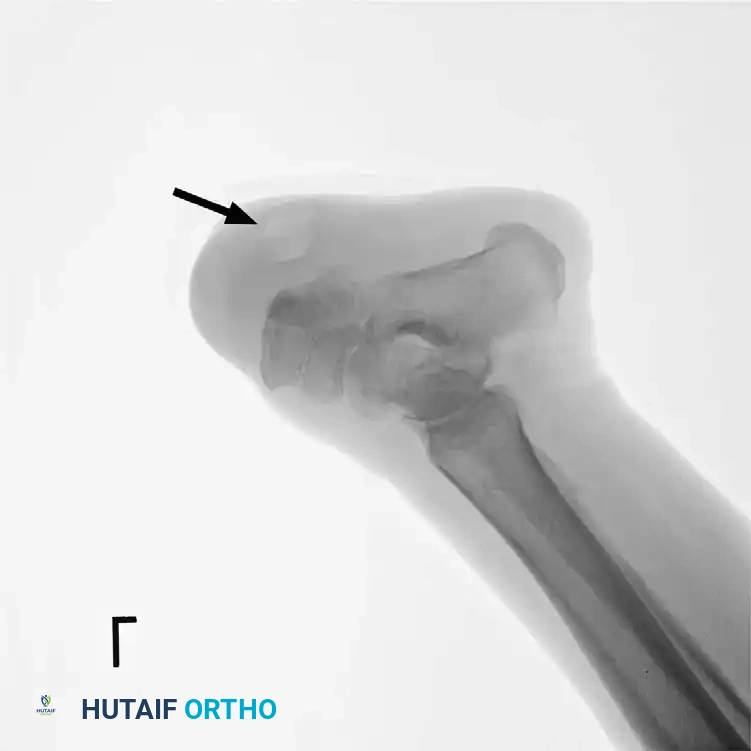

Severe equinus deformity

Recurrent seroma on lateral radiograph